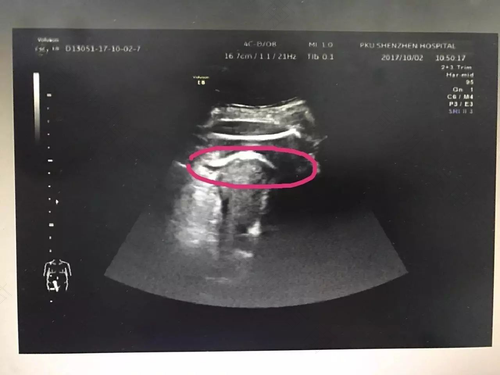

子宫破裂的超声表现:

1.直接表现:大部分都是子宫下段,子宫正常情况下分为三层:从外到内依次为脏层覆膜反折,回肌层及绒毛膜。当子宫下段受羊水的流动,胎动、宫缩等影响观察到羊膜囊向膀胱膨胀,可能出现先兆子宫破裂。如果肌层中断是子宫破裂的征兆。

2.间接表现:腹腔血肿不规则强回声及积液。